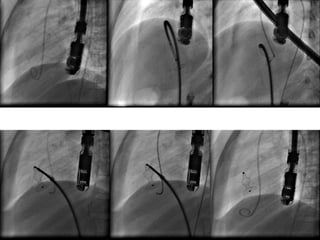

• 108.

AMPLATZER Muscular VSD Occluder 108 Self-expandable Nitinol mesh with polyester patches conform to the ventricular septum  Waist length: 7mm  Sizes: 4-18mm Device Size (Waist = A) Right Ventricular Disc (B) Left Ventricular Disc (C) Length of Waist (D) Legend Device Size (Waist = A) 4 6 8 10 12 14 16 18 RV Disc (B) 9 14 16 18 20 22 24 26 LV Disc (C) 9 14 16 18 20 22 24 26 Length of Waist (D) 7 7 7 7 7 7 7 7

• 109.

Advantages  Waist isbroad  Used upto 16-17 mm  Even in those with PHT

• 110.

Disadvantages  Not designedfor PMVSD closure  Larger sheath  Encroachment on the LVOT and aortic valve  TV mechanism

• 111.

Exclusion  Small children Large VSDs  Significant aortic valve prolapse  More than mild AR  Down’s syndrome  Severe PHT